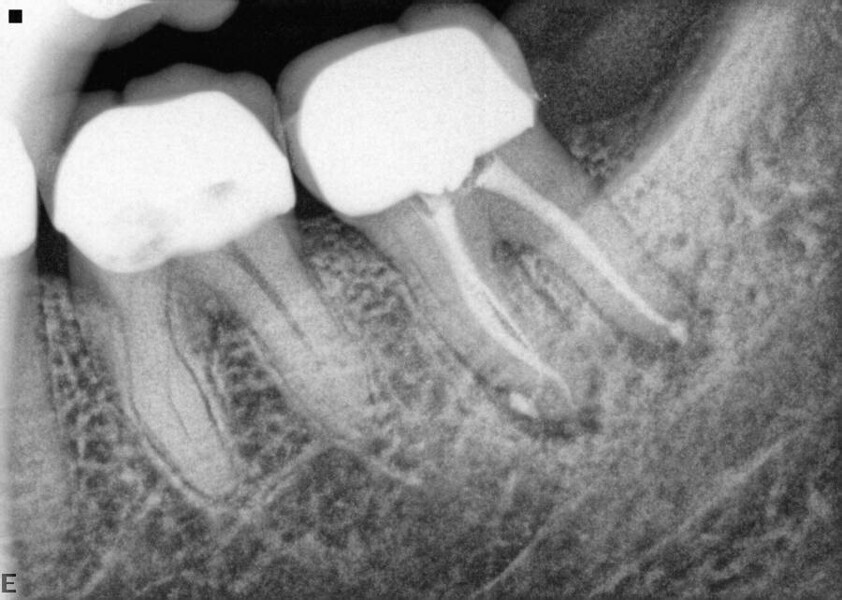

Fig. 14a: Case treated with Bassi Logic controlled memory nickel titanium files. Note the visualization of the third root on this lower molar and conservative canal preparation shape. (Courtesy of Dr. Alex Chan)

Fig. 14b: Case treated with Bassi Logic controlled memory nickel titanium files. Note the visualization of the third root on this lower molar and conservative canal preparation shape. (Courtesy of Dr. Alex Chan)